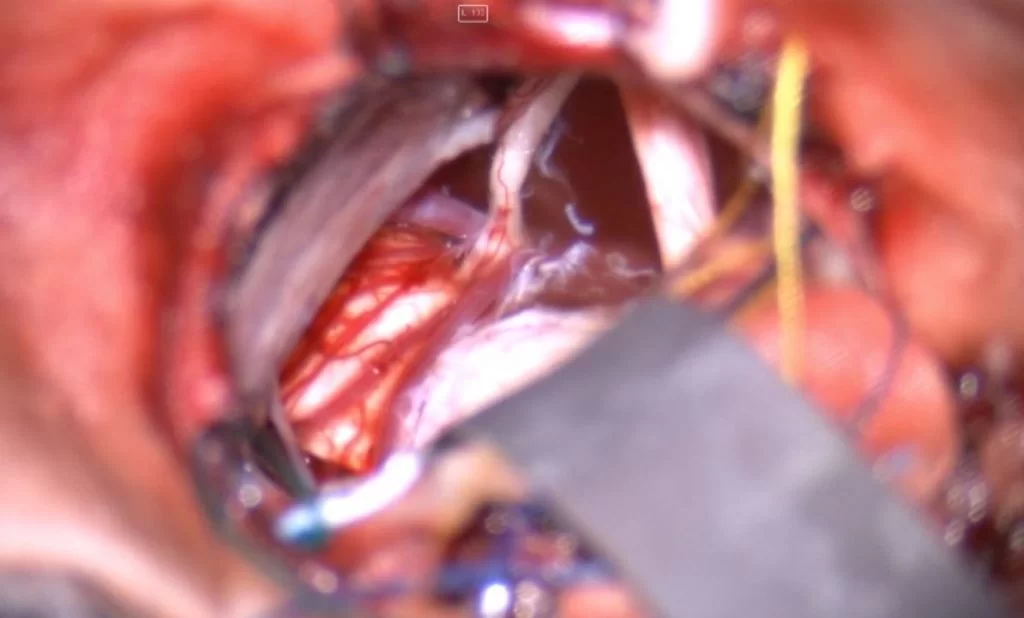

Διενεργήθη οπισθοσιγμοειδική οστεοπλαστική προσπέλαση και ολική εξαίρεση της βλάβης.

Οι επιδερμοειδείς κύστεις είναι απολύτως καλοήθεις όγκοι, οι οποίοι αναπτύσσονται αργά αλλά σταθερά. Το πρόβλημα συχνά είναι ότι τη στιγμή που γίνονται αντιληπτοί έχουν ήδη λάβει μεγάλες διαστάσεις, ενώ μια από τις συνηθέστερες εστίες ανάπτυξής τους -η λεγόμενη γεφυροπαρεγκεφαλιδική γωνία- είναι μια “χειρουργικά απαιτητική” περιοχή της βάσης του κρανίου με πολλά και σημαντικά ανατομικά στοιχεία (δηλαδή με πολλά και σημαντικά νεύρα και αγγεία).

Σε τέτοιες βλάβες είναι εξαιρετικά σημαντική η εμπειρία του νευροχειρουργού στη χειρουργική των όγκων της βάσης κρανίου. Σημαντικά βοηθήματα είναι ο διεγχειρητικός νευροφυσιολογικός έλεγχος και η χρήση του ενδοσκοπίου προκειμένω να ελεγχθούν ακόμα και “κρυφά” σημεία του χειρουργικού πεδίου.